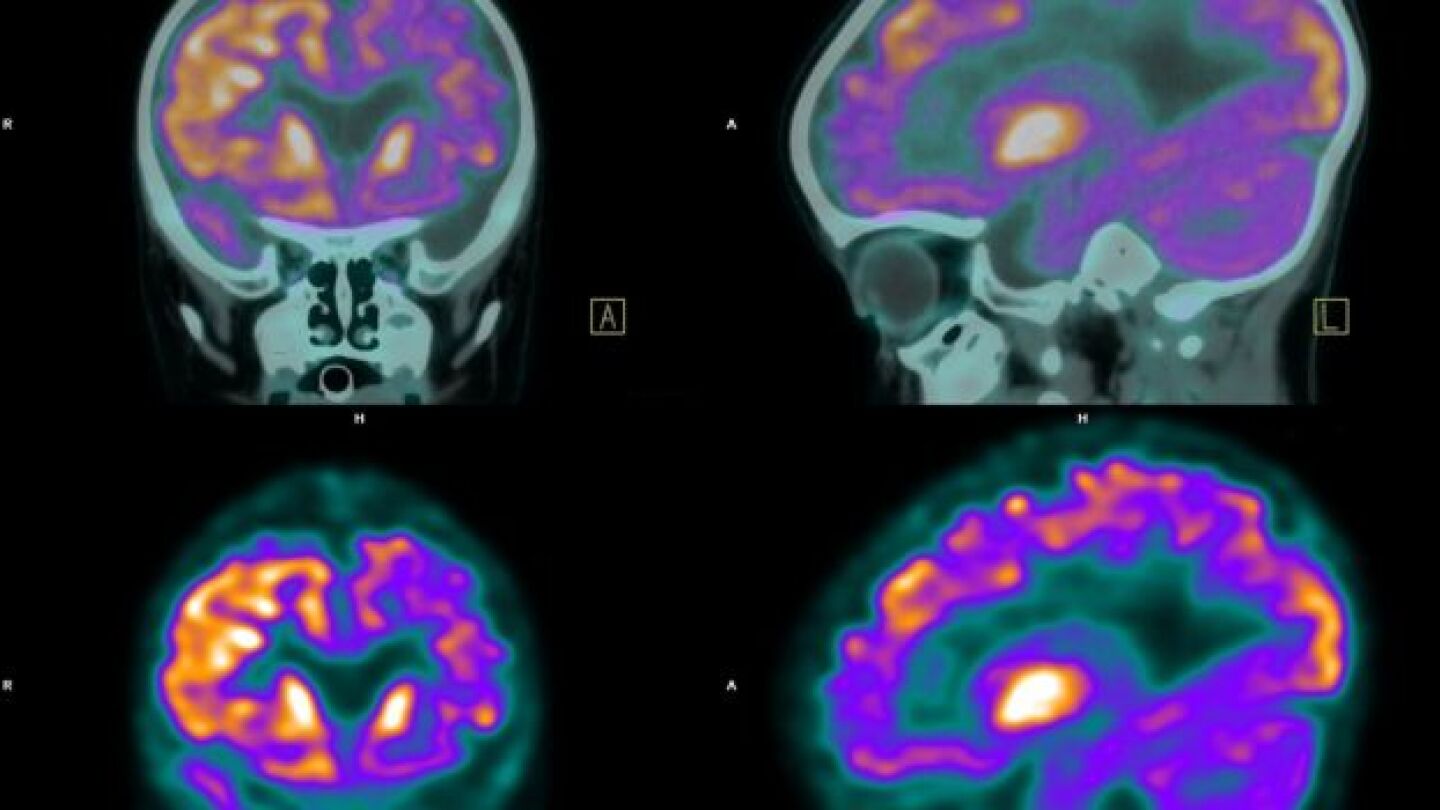

Brain cancer